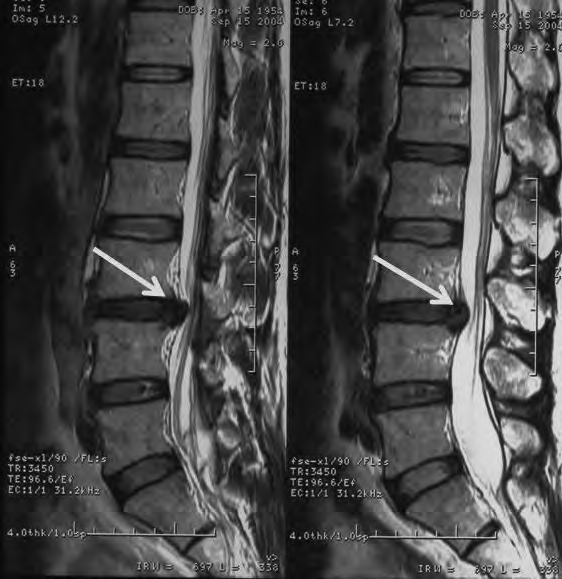

Na obrazie rezonansu magnetycznego strzałką oznaczono patologiczny kręg

A. L1

B. TH10

C. L3

D. TH8

Na obrazie RM uwidoczniono odcinek kręgosłupa

A. Th w przekroju czołowym.

B. L w przekroju czołowym.

C. L w przekroju strzałkowym.

D. Th w przekroju strzałkowym.